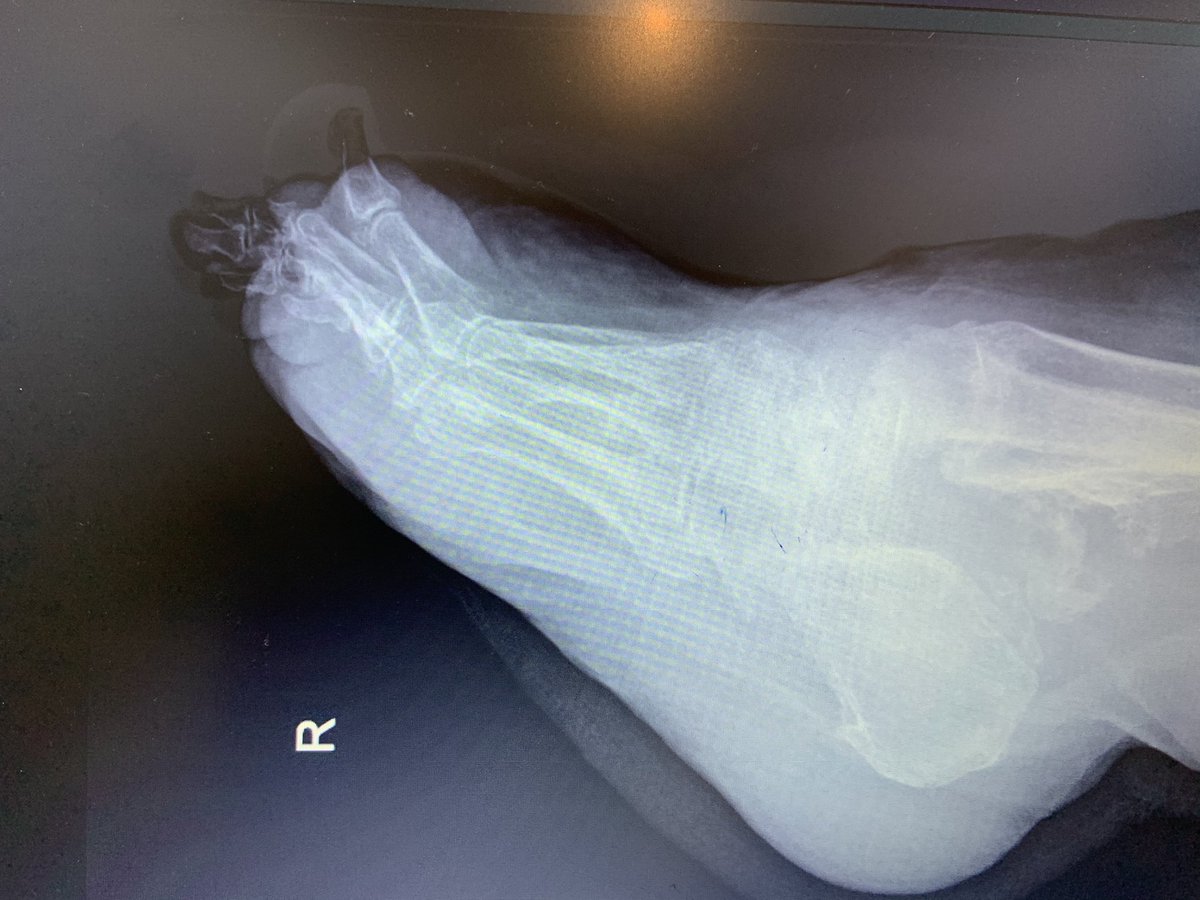

هي عبارة عن كسور تصيب القدم السكرية نتيجة اعتلال الأعصاب الطرفية السفلية وفقدان الإحساس.وتختلف تماما عن الكسور العادية.

غالباما يسبق حدوث قدم شاركوت إصابة بالقدم أوالكاحل ونظرا لضعف الإحساس في القدم ، مريض السكر يستمر بالمشي على قدمه مما يؤدي الى تكسر في عدة عظام أو خلع في المفاصل.

إذا تم التشخيص في مرحلة مبكرة قبل حدوث تكسر في العظام أو خلع في المفاصل فنسبة المحافظة على القدم تكون عالية وتقلل نسبة المضاعفات.

الأعراض المبدئية لقدم شاركوت تشمل تورم، احمرار وألم في القدم أو الكاحل وغالبا الأشعة السينية تكون سالبة في هذه المرحلة، ونظرا لقلة خبرة الأطباء بقدم شاركوت فلا يتم التشخيص المبكر. وغالبا يصل المريض الى الطبيب المختصص في مرحلة متأخرة.